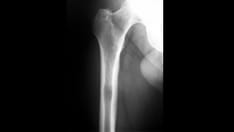

In skeletal traction, a pin (eg, a Steinmann pin) is placed through a bone distal to the fracture. Weights are applied to this pin, and the patient is placed in an apparatus to facilitate traction and nursing care. Skeletal traction is most commonly used in femur fractures: A pin is placed in the distal femur (see the image below) or proximal tibia 1-2 cm posterior to the tibial tuberosity. Once the pin is placed, a Thomas splint is used to achieve balanced suspension.

Locked intramedullary nails provide relative stability to maintain bone alignment and length and to limit rotation. Ideally, intramedullary nailing allows for compressive forces at the fracture site, which stimulates bone healing. Intramedullary nails are commonly used for femoral and tibial diaphyseal fractures (see the image below) and, occasionally, humeral diaphyseal fractures. The advantages of intramedullary nails include minimally invasive procedures, early postoperative ambulation, and early ROM.

Midshaft femur fracture managed with open reduction and internal fixation performed with use of an intramedullary nail.

Femur fracture managed with skeletal traction and use of a Steinmann pin in the distal femur.